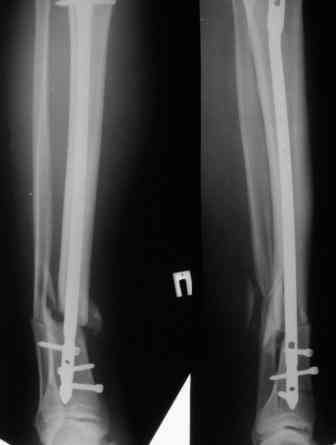

Давность травмы 3 недели. Синтез 17.10.2006. На счет большего угла: гипс наложен сразу после травмы - по разнице углового смещения можно судить о подвижности отломков и величине деформации.Сторонники варианта 4 ссылаются на данные мировой литературы(?), в которых якобы 50% интрамедуллярного остеосинтеза голени обходится без дистального блокирования.Неуверен о каких штифтах и переломах идет речь, но по-моему представленный случай не из этой серии.

Да, с устранением деформации проблем не должно быть. Но как будете вводить дистальные винты опять без усилителя рентгеновского изображения? Может, есть возможность перевести пациента для этой манипуляции в РКБ? Я слышал, там теперь есть ЭОП.

Конечно. Тут скорее в длинный проксимальный отлмок можно ую не вводить винты, а дистальный - короткий и широкий, стержень там без винтов как карандаш в стакане.